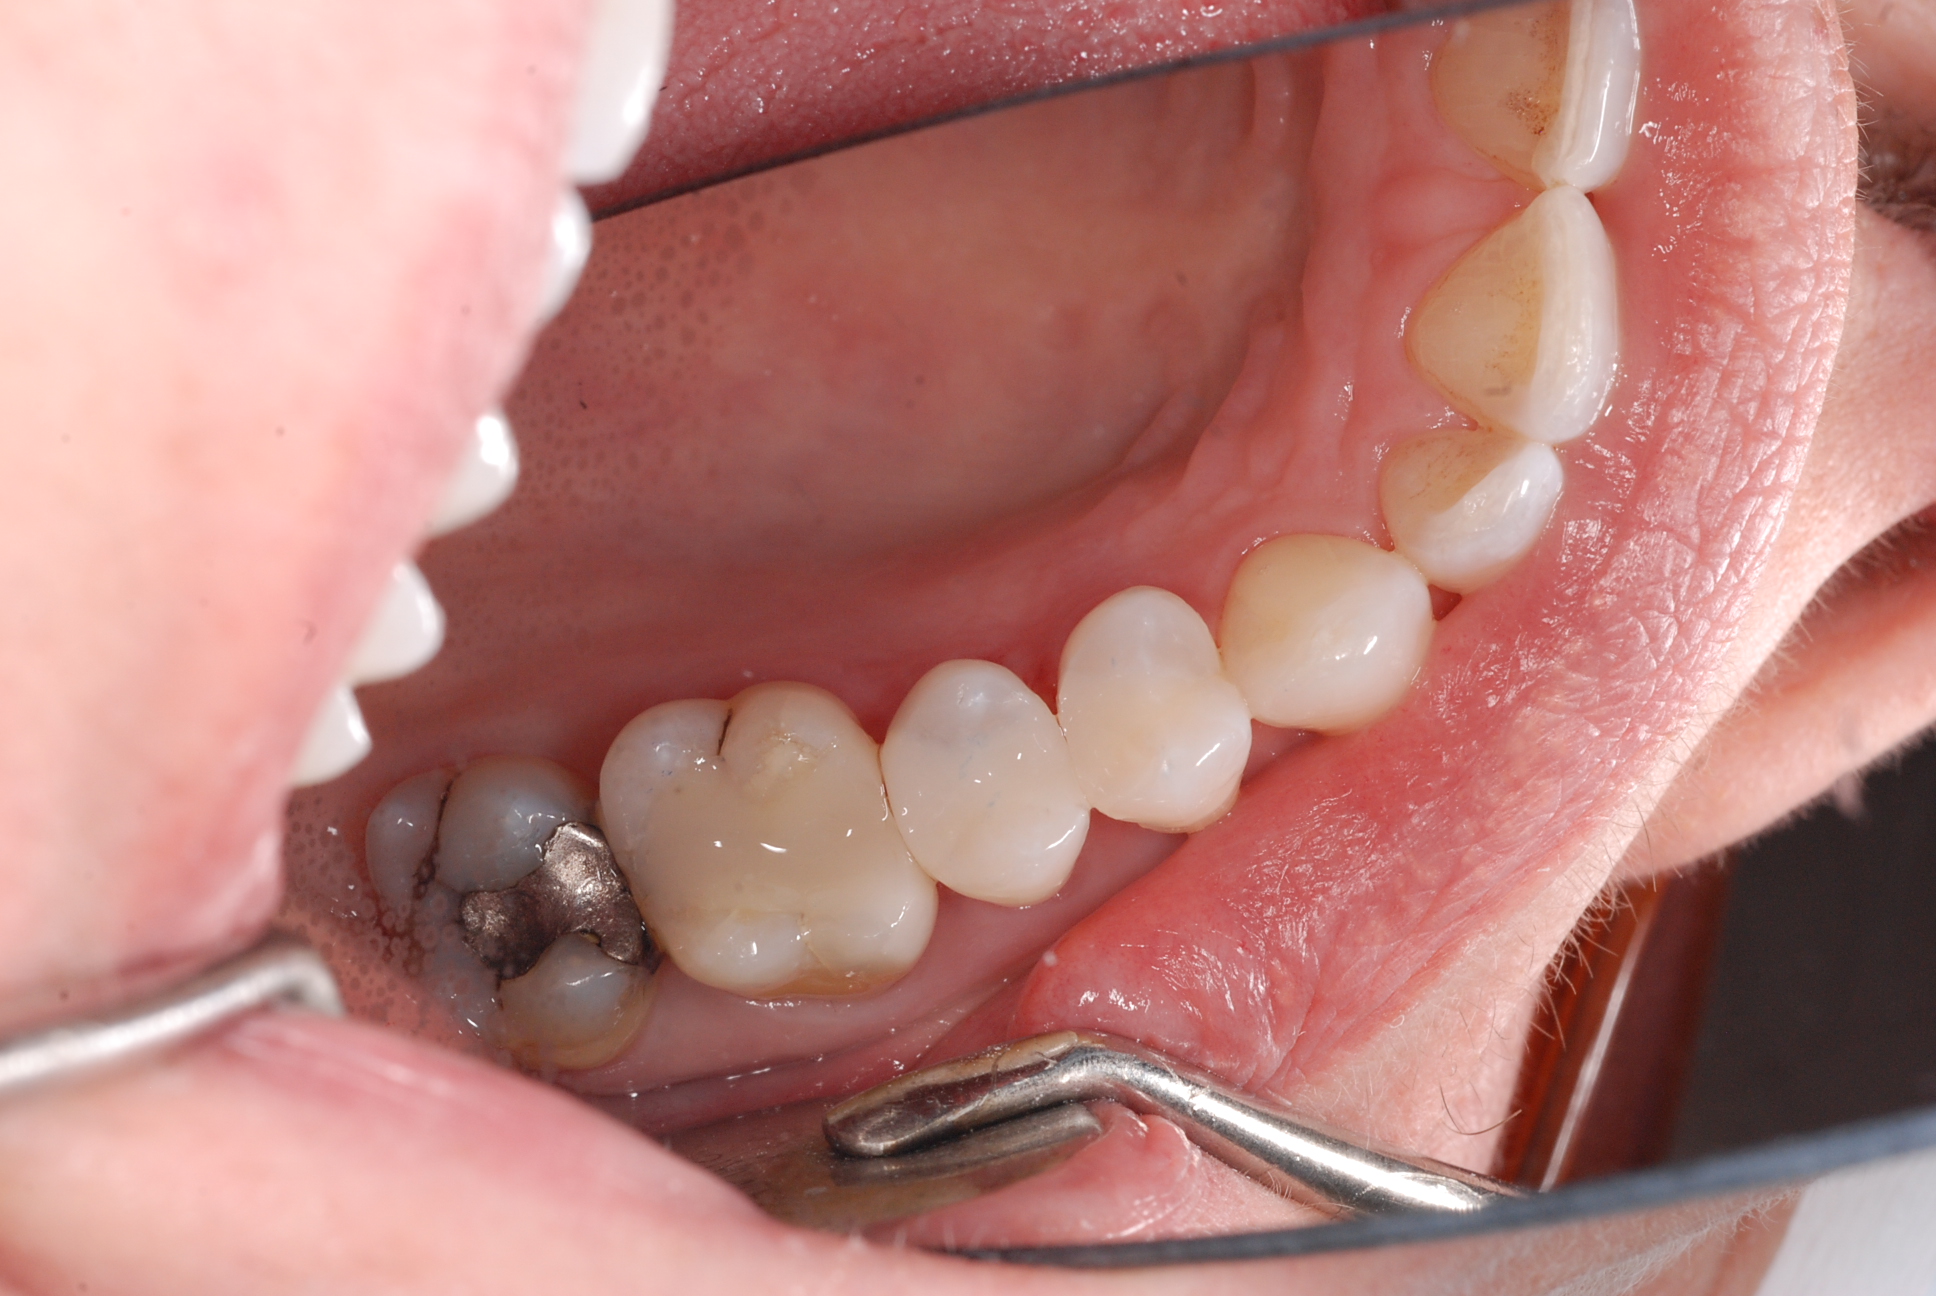

Silver amalgam ( dental amalgam ) has been filled into patient’s teeth for a hundred years, and no one seems to have worried that these fillings corrode like any metal in a moist and tough environment. Corrosion products cause ‘rust like material’ to be absorbed into the inner structures of the tooth and if left untreated, cracks develop in the base of the cavity causing pain and sensitivity. ‘Cracked tooth syndrome’ is a vexing problem of cracked teeth. A beautiful smile begins to age, look gray and lifeless.

At Caring 4 Smiles we brighten patient’s smiles and reduce the risk of cracked teeth by removing amalgam fillings and replacing them with beautiful white bonded composite fillings. Larger fillings are replaced with porcelain crowns or inlays made using the latest CEREC CAD-CAM technology. We fit ‘crowns in a day’ with CEREC technology. It’s truly amazing.